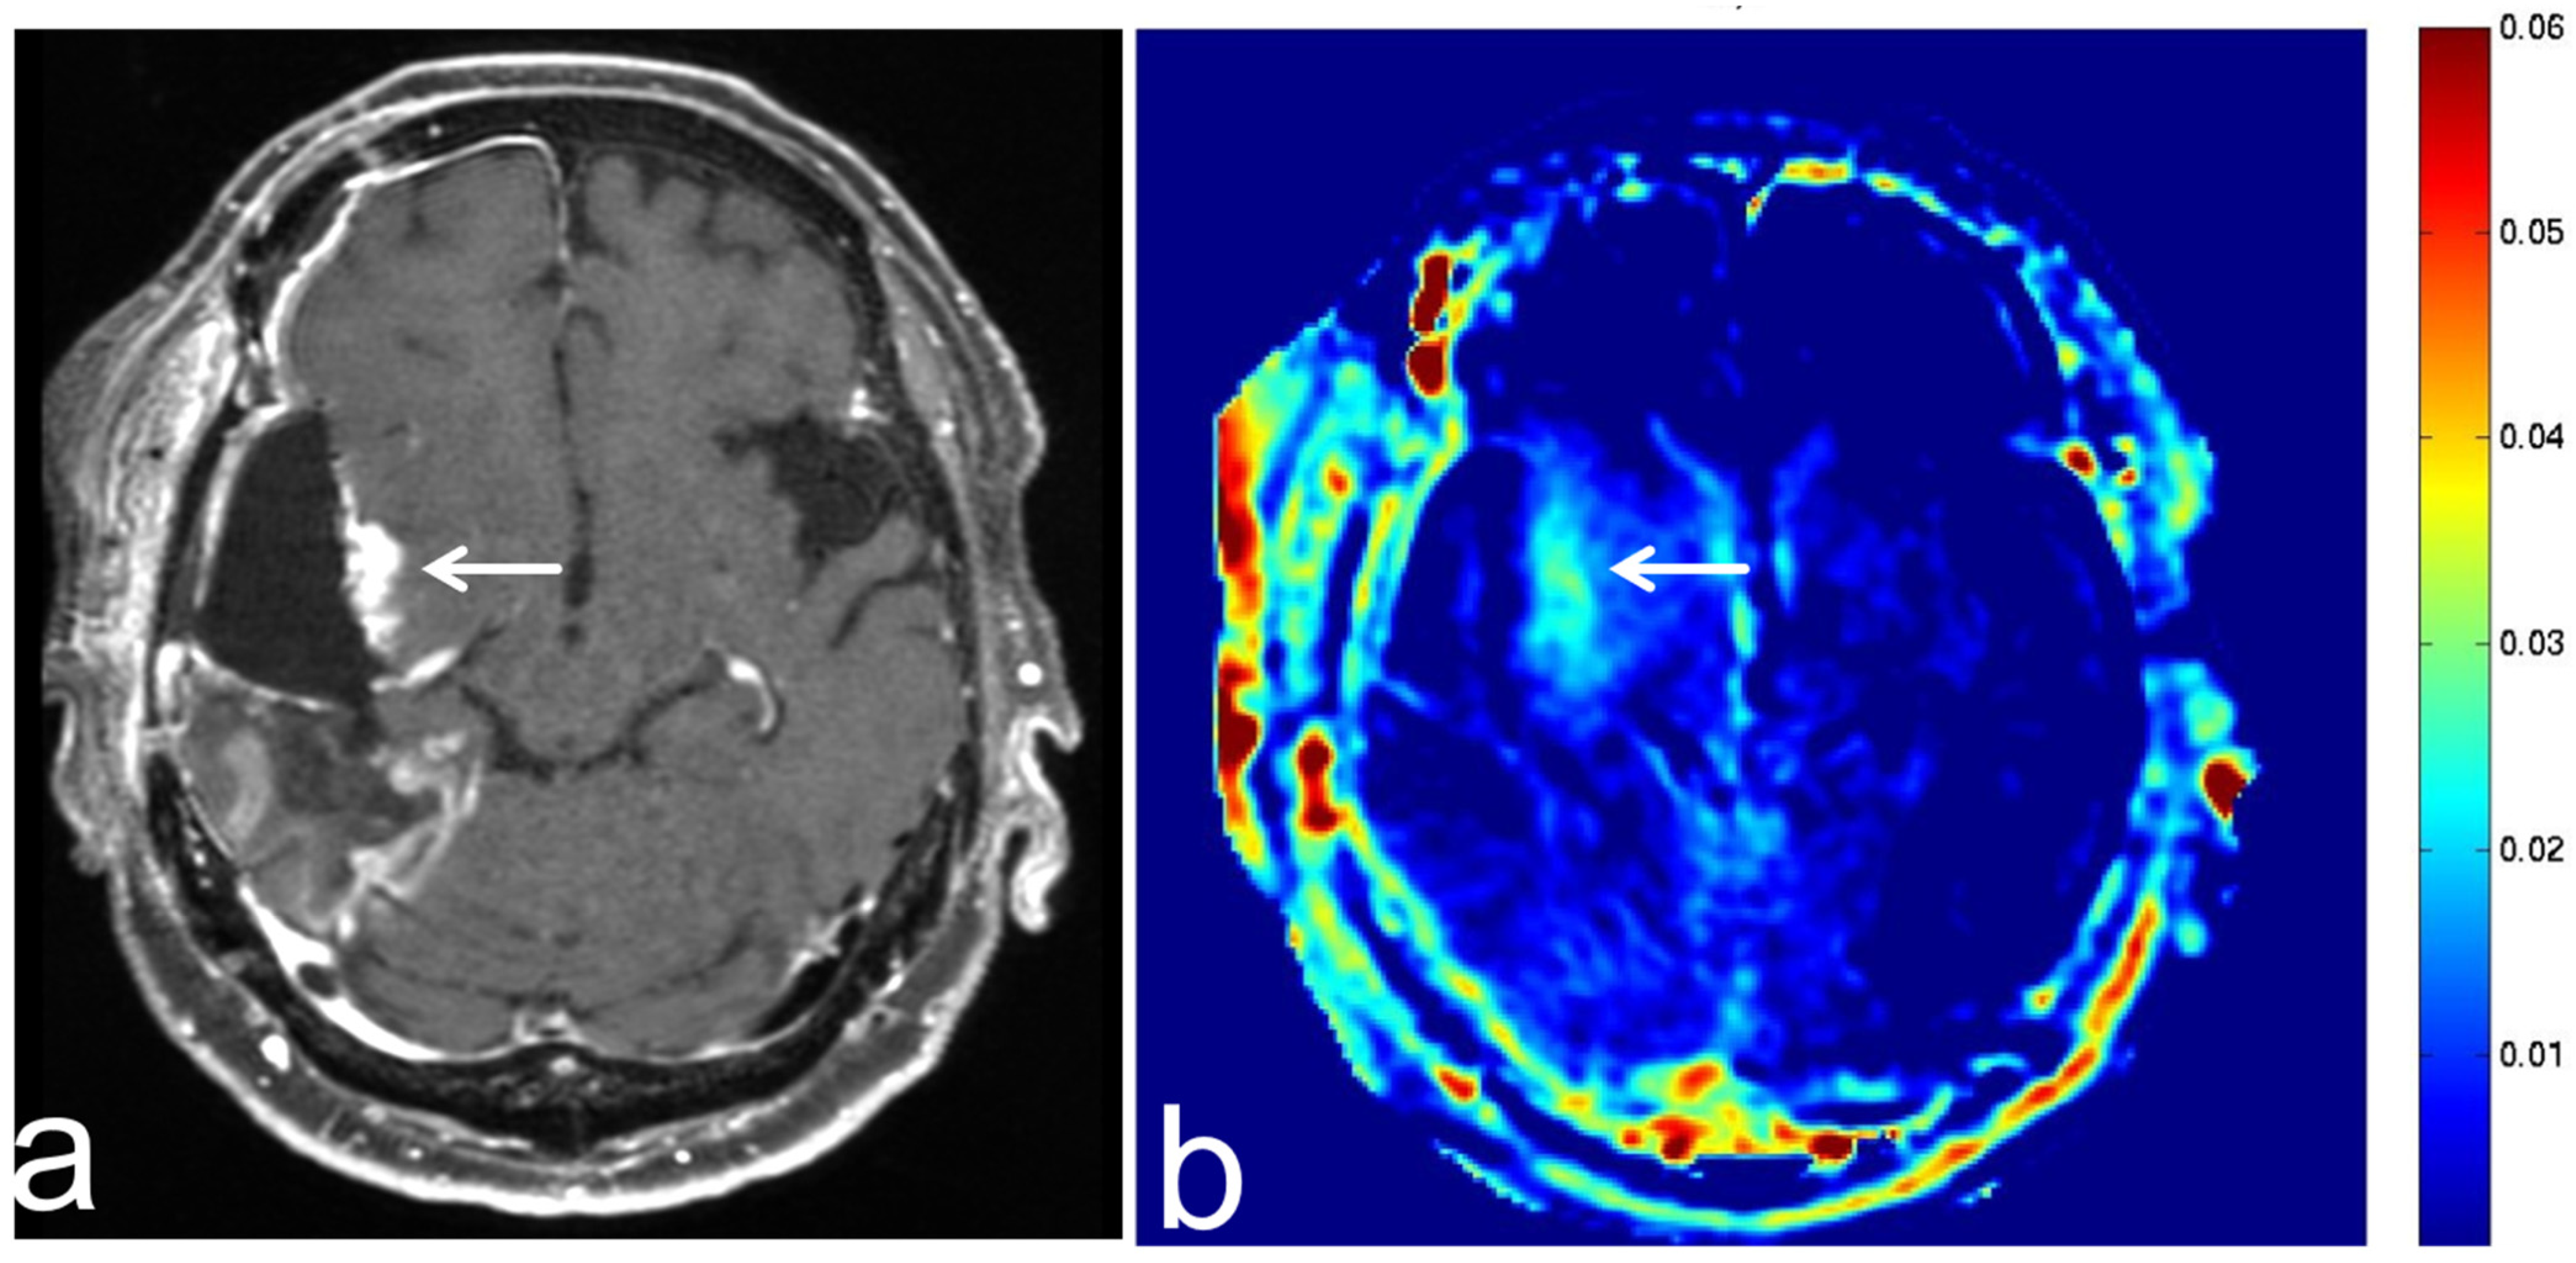

8.1. Radiation Necrosis